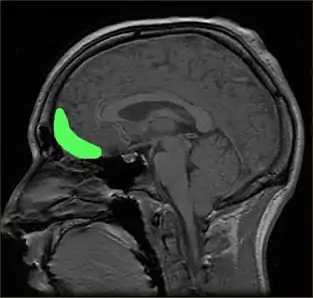

Impulsivity is both a facet of personality and a major component of various disorders, including FASD, ADHD,[7] substance use disorders,[8][9] bipolar disorder,[10] antisocial personality disorder,[11] and borderline personality disorder.[10] Abnormal patterns of impulsivity have also been noted instances of acquired brain injury[12] and neurodegenerative diseases.[13] Neurobiological findings suggest that there are specific brain regions involved in impulsive behavior,[14][15][16] although different brain networks may contribute to different manifestations of impulsivity,[17] and that genetics may play a role.[18]

Although the precise neural mechanisms underlying disorders of impulse control are not fully known, the prefrontal cortex (PFC) is the brain region most ubiquitously implicated in impulsivity.[143] Damage to the prefrontal cortex has been associated with difficulties preparing to act, switching between response alternatives, and inhibiting inappropriate responses.[137] Recent research has uncovered additional regions of interest, as well as highlighted particular subregions of the PFC, that can be tied to performance in specific behavioral tasks.